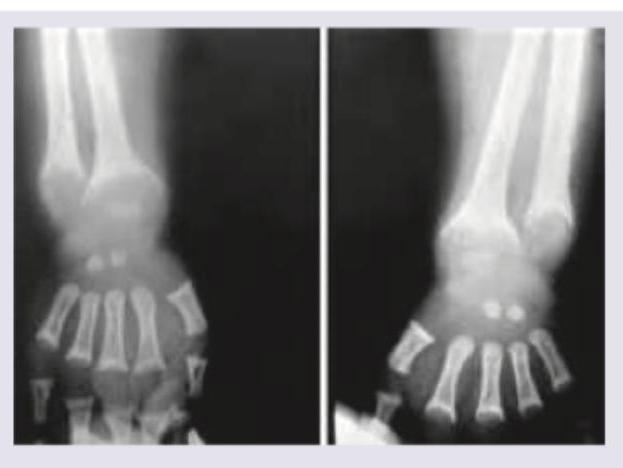

A 5-year-old boy from upper socioeconomic background presents with bowing of legs. On work up serum calcium was $9 \mathrm{mg} \%$ with serum phosphate of $1 \mathrm{mg} \%$ with normal serum alkaline phosphatase (ALP) and normal serum PTH. X-ray wrist joint is given. Comment on the diagnosis:

Explanation: ***Hypophosphatemic rickets*** - The classic presentation of **bowing of the legs** (rickets) in a child with **isolated low serum phosphate** (1 mg%), normal calcium and PTH, points directly to hypophosphatemic rickets. - The **X-ray of the wrist joint** would likely show characteristic findings of rickets such as **widening and fraying of growth plates**, confirming the diagnosis. *Bartter syndrome* - This is a rare genetic disorder affecting the kidneys, leading to **salt wasting**, **hypokalemic metabolic alkalosis**, and normal to low blood pressure. - It does not primarily cause rickets or the specific electrolyte imbalance seen here (isolated hypophosphatemia). *Chronic renal failure* - While chronic renal failure can lead to renal osteodystrophy (a form of rickets), it would typically involve **elevated PTH**, **hyperphosphatemia (initially)** or varied calcium levels, and often metabolic acidosis. - In this case, PTH is normal and phosphate is low, making chronic renal failure less likely. *Polycystic kidneys* - This is a genetic disorder characterized by the growth of numerous cysts in the kidneys, which can cause kidney dysfunction over time. - However, it does not directly present with isolated **hypophosphatemia** and bone bowing in a 5-year-old without other clear signs of significant renal failure.